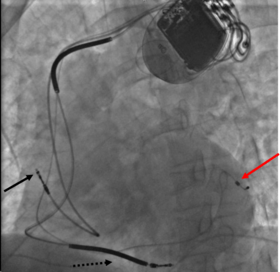

Biventricular pacing

Cardiac resynchronization therapy (CRT) is used for people with heart failure in whom the left and right ventricles do not contract simultaneously (ventricular dyssynchrony), which occurs in approximately 25–50% of heart failure patients. To achieve CRT, a biventricular pacemaker (BVP) is used, which can pace both the septal and lateral walls of the left ventricle. By pacing both sides of the left ventricle, the pacemaker can resynchronize the ventricular contractions.

CRT devices have at least two leads, one passing through the vena cava and the right atrium into the right ventricle to stimulate the septum, and another passing through the vena cava and the right atrium and inserted through the coronary sinus to pace the epicardial wall of the left ventricle. Often, for patients in normal sinus rhythm, there is also a lead in the right atrium to facilitate synchrony with the atrial contraction. Thus, timing between the atrial and ventricular contractions, as well as between the septal and lateral walls of the left ventricle can be adjusted to achieve optimal cardiac function.

CRT devices have been shown to reduce mortality and improve quality of life in patients with heart failure symptoms; a LV ejection fraction less than or equal to 35% and QRS duration on EKG of 120 ms or greater.[37][38]

Biventricular pacing alone is referred to as CRT-P (for pacing). For selected patients at risk of arrhythmias, CRT can be combined with an implantable cardioverter-defibrillator (ICD): such devices, known as CRT-D (for defibrillation), also provide effective protection against life-threatening arrhythmias.[39]